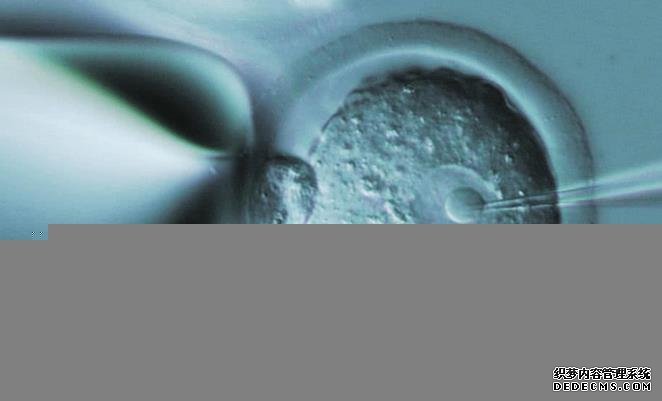

且供卵试管婴儿费用主要由检查、培育以及移植等环节的花费和卵源补助组成,具体情况如下:

1、检查:在试管婴儿前期和有卵源时,医生会分别安排一次身体检查,主要包括各种常规检查,需要大约5000-8000元;

2、培育:患者等到卵源,并受精完成后,即可开始早期胚胎培育,费用需要3000元左右;

3、移植:早期胚胎培育完成,医生会根据女方身体确认移植方案,需要大约3000-8000元;

4、卵源补助:供卵试管的卵子由第三方女性捐赠,可给予一定的误工、交通和医疗补助。我之前以为供卵试管不用做促排,费用就会更便宜一些,但没想到这个花费也不低,就想请问一下检查、培育以及移植这三个部分的费用可以报销吗供卵试管婴儿中各个环节的费用都不能报销,因为湖北省并未将人类辅助生殖技术纳入医保范围,所以不管是在武汉大学人民医院还是省内其他生殖机构做试管的花费都需要自己承担。且在国内只有北京可报销部分试管费用,但也仅限于部分项目。